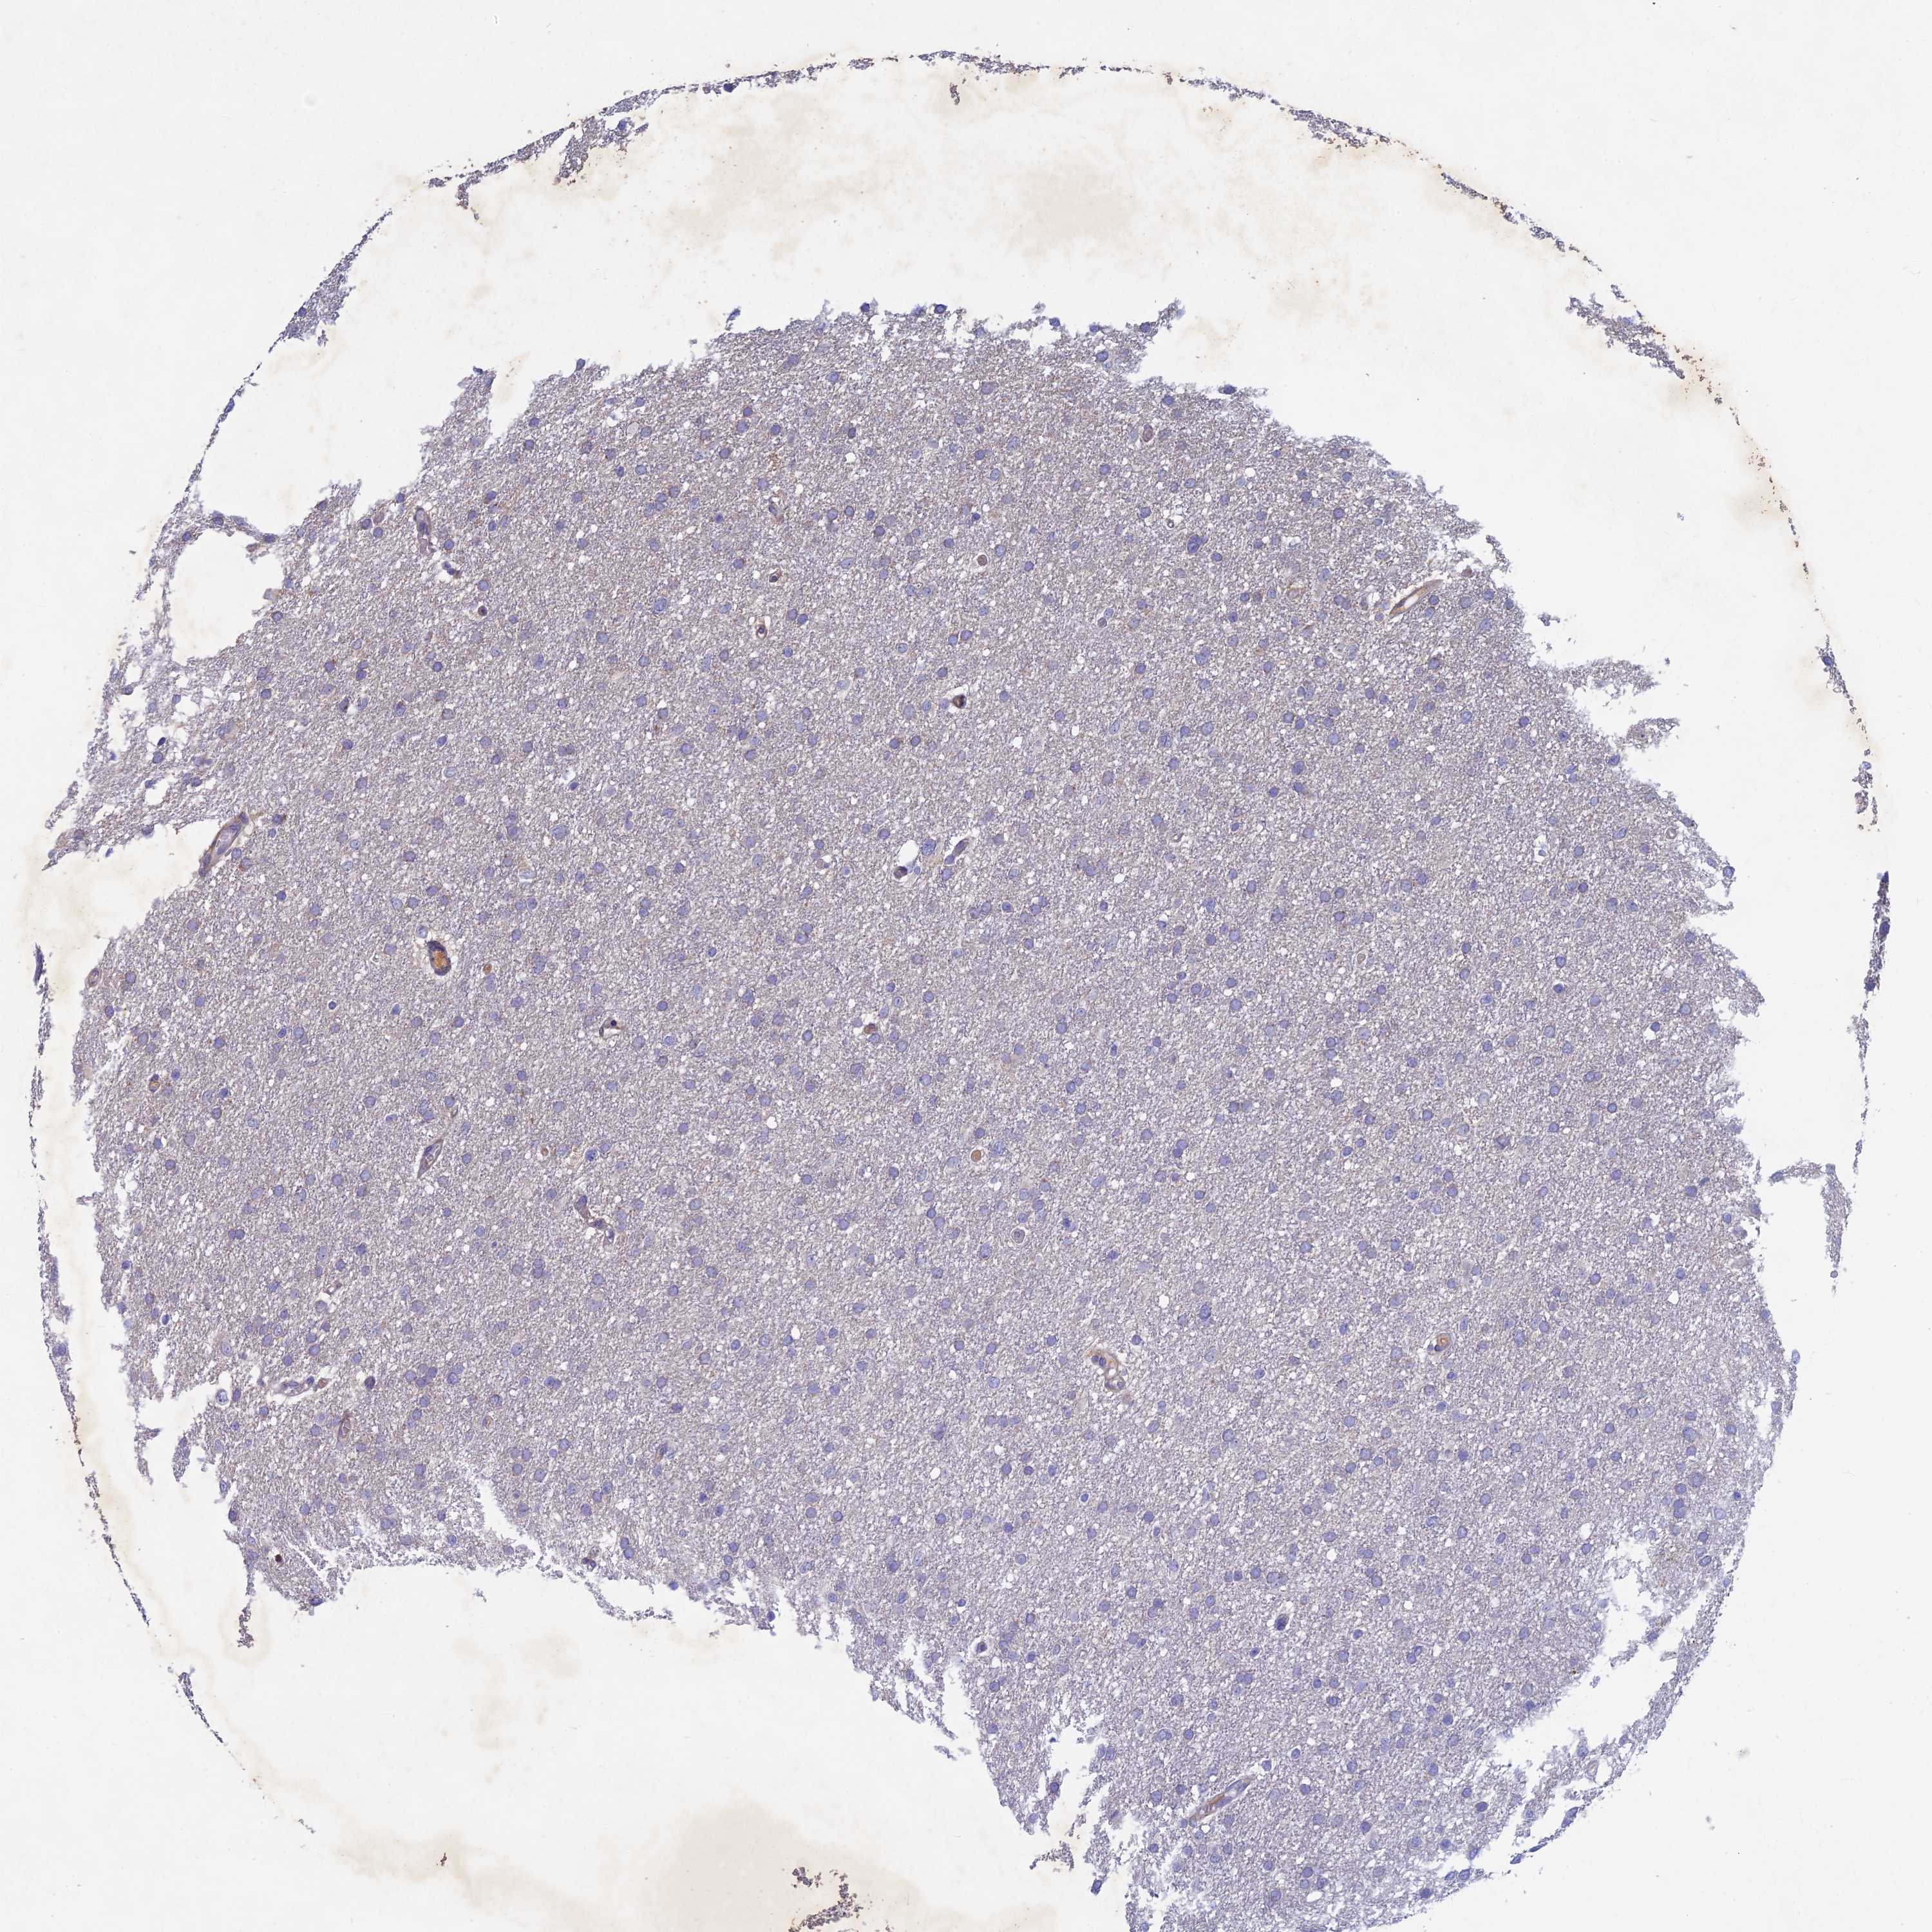

GLIOMA - Protein expressioni

A mouse-over function shows sample information and annotation data. Click on an image to view it in a full screen mode. Samples can be filtered based on level of antibody staining by selecting one or several of the following categories: high, medium, low and not detected. The assay and annotation is described here.

Note that samples used for immunohistochemistry by the Human Protein Atlas do not correspond to samples in the TCGA dataset.

Antibody stainingi

Antibody staining in the annotated cell types in the current human tissue is reported as not detected, low, medium, or high, based on conventional immunohistochemistry profiling in selected tissues. This score is based on the combination of the staining intensity and fraction of stained cells.

Each image is clickable and will lead to virtual microscopy that enables deeper exploration of all samples and also displays staining intensity scores, fraction scores and subcellular localization as well as patient and tissue information for each sample.

Antibody HPA041994

Staining

High

Medium

Low

Not detected

Intensity

Strong

Moderate

Weak

Negative

Quantity

>75%

75%-25%

<25%

None

Location

Nuclear

Cytoplasmic/membranous

Cytoplasmic/membranous,nuclear

Glioma, malignant, High grade

Glioma, malignant, Low grade